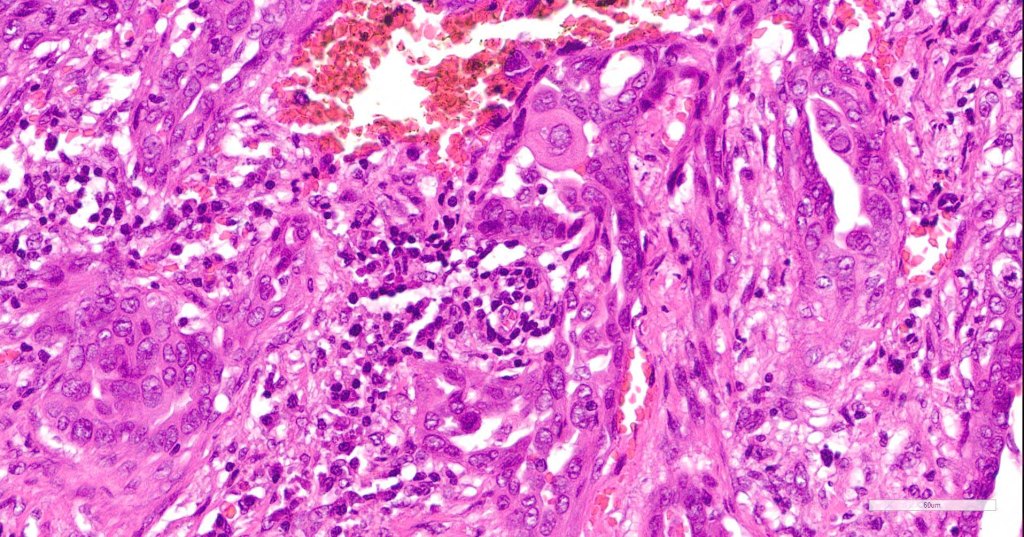

•Superficial SCC

•Adenocarcinoma in deeper reaches

•Variable pleomorphism and mitotic activity

•Deep part may show both ducts and glands

•Perineural infiltration is commonly seen